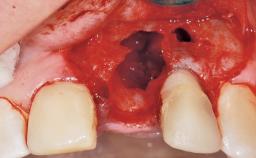

Immediate Flapless Placement of an Implant in a Maxillary Left Central Incisor Site

A 29-year-old female patient presented for treatment to replace the upper left central incisor tooth with an implant- supported restoration. The tooth had been intermittently symptomatic for the previous 12 months. The tooth had originally suffered trauma about 15 years previously. Several endodontic treatments had been performed, including an apicectomy procedure to retain the tooth. The patient was healthy and a non-smoker. She had reasonable expectations in regard to esthetic outcomes and the risk of marginal tissue recession following treatment. At medium smile, the gingival margins of the upper teeth were visible, with a display of 3 to 4 mm of the gingival margins. Gingival recession of tooth 21 and a discrepancy in the gingival levels between teeth 11 and 21 was observable during normal speech and smile.

| Socket Integrity | Damage to one or more bone walls |

| Bone Volume | Damage to one or more socket walls |

| Risk of Complications | High |